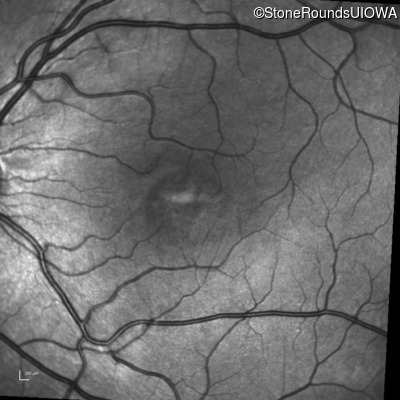

Infrared Fundus Photograph - Right - 20/50

Exemplar